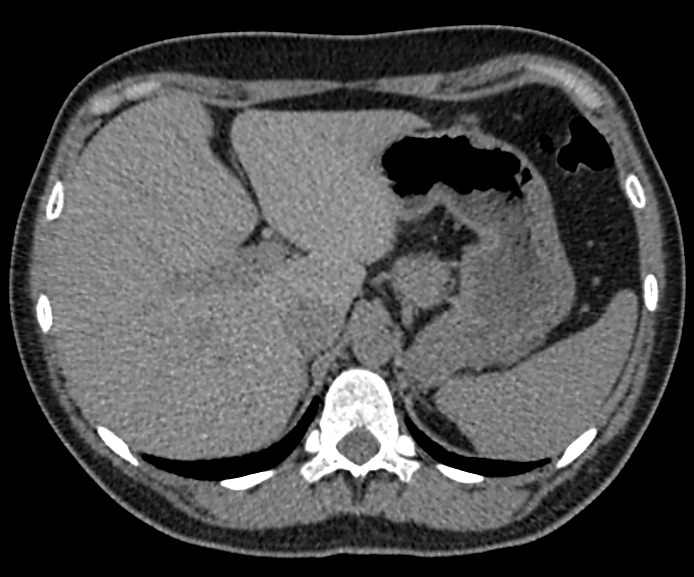

Мультиспиральная компьютерная томография селезенки – высокоинформативный инструментальный метод исследования, основанный на использовании рентгеновского излучения и позволяющий детально визуализировать паренхиму селезенки, состояние близлежащих органов и тканей, питающих ее кровеносных сосудов и лимфоузлов.

МСКТ селезенки проводится как с использованием контраста, так и без него. Контрастирование применяется для выявления патологических очагов, которые могут быть не видны при нативном исследовании. Для этого внутривенно вводится контрастный препарат, содержащий йод и накапливающийся в патологических очагах опухолевой и воспалительной природы.

Нативная КТ (бесконтрастное исследование селезенки) показывает структуру органа достаточно однородно, без выявления незначительных изменений. Для большей информативности делают КТ селезенки с применением контрастных веществ.

На томограмме можно увидеть:

- нарушение целостности селезенки;

- кисты и крупные опухоли;

- кальцинаты;

- травматические и посттравматические изменения селезенки

- кровоизлияния внутрь брюшной полости

- отклонения от нормальных размеров.

- дополнительные дольки селезенки.